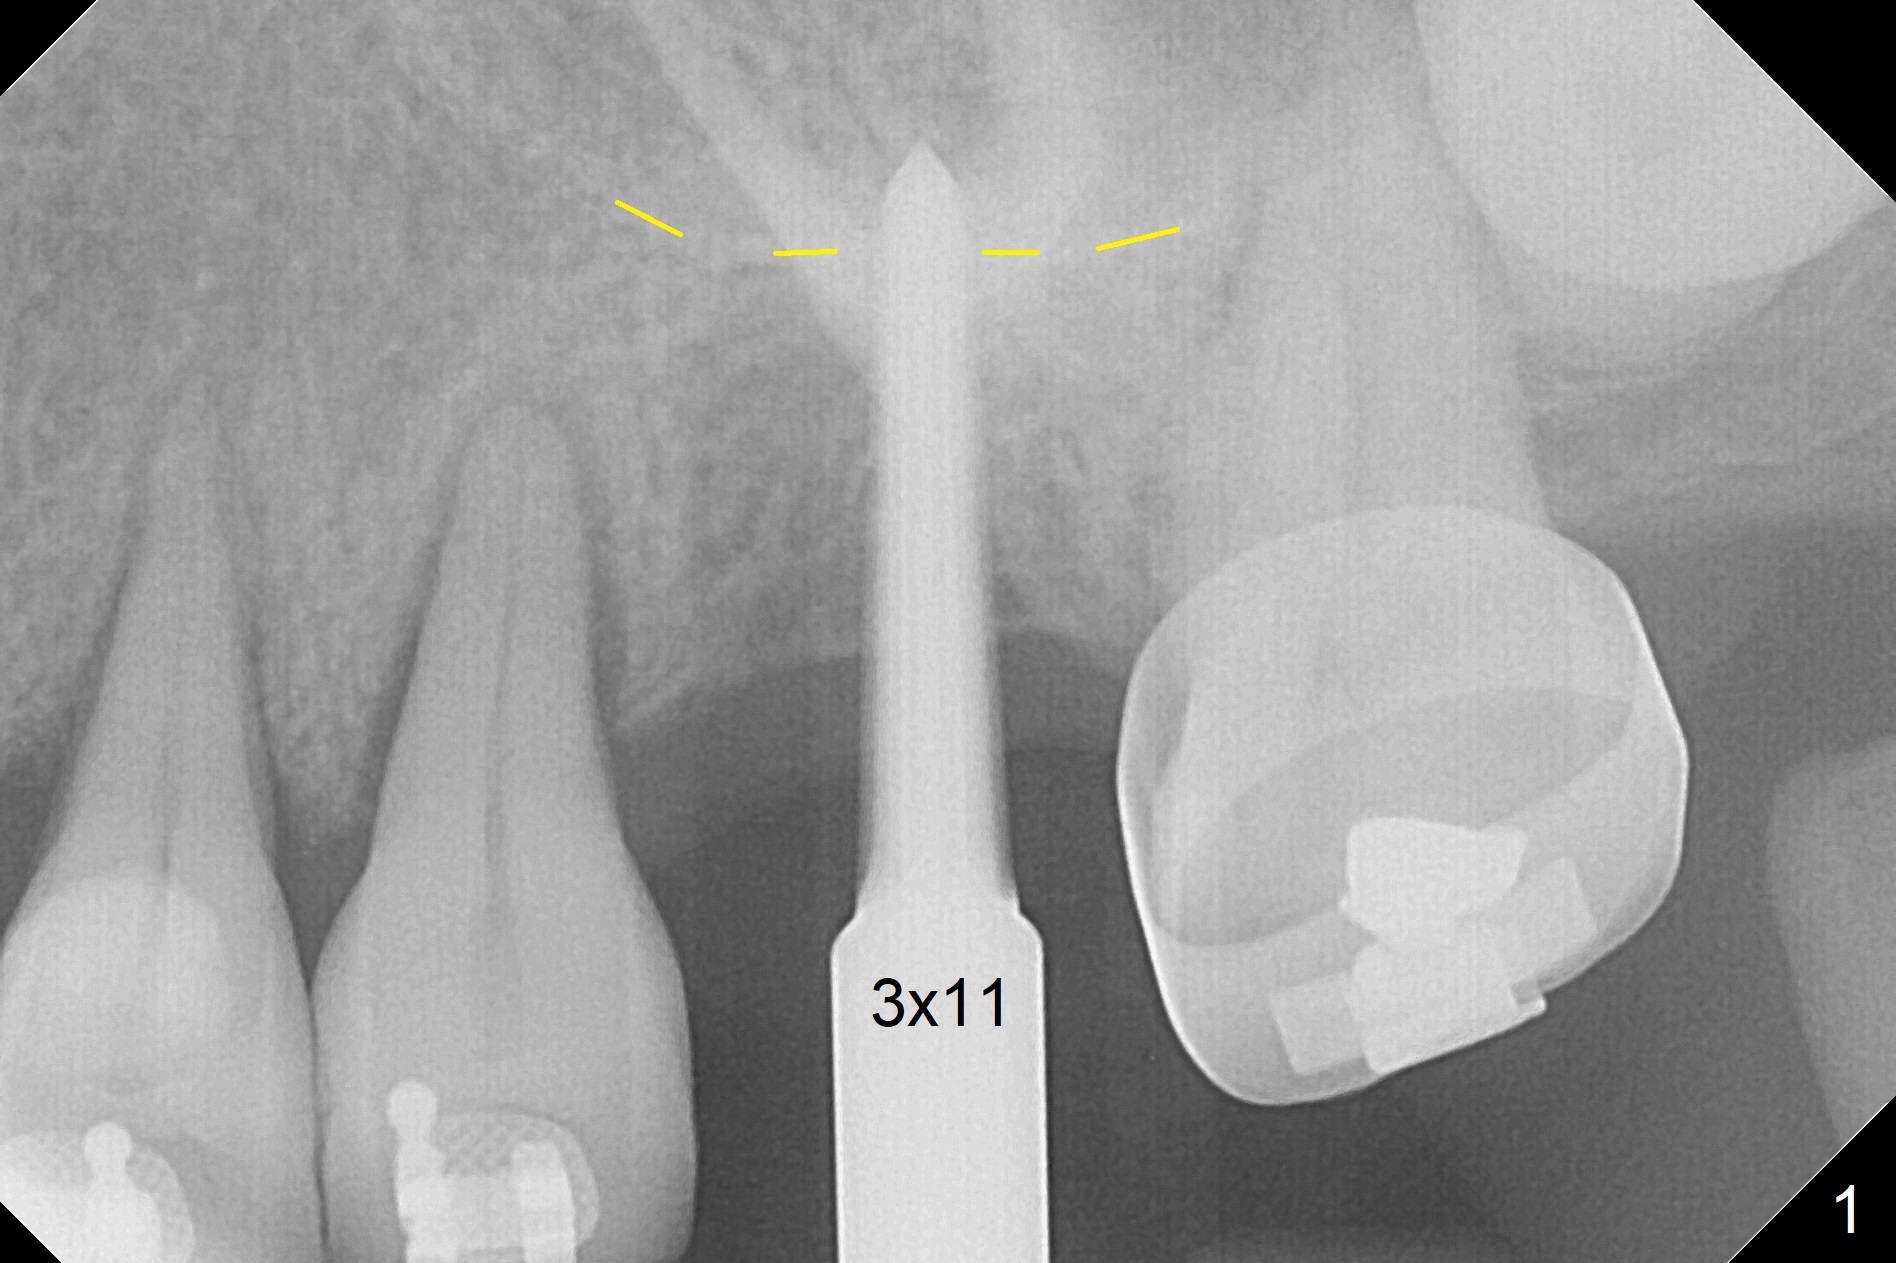

Preop exam shows the narrow ridge at #14. Magic split is used for access and initiation of osteotomy and bone expansion, followed by 3 mm Magic Expander for 11 mm (ME, Fig.1 (yellow line: sinus floor)). In fact the bone is soft. After use of 3.8 mm ME and Lindamann bur (to move the osteotomy distobuccally), a 4x11 mm dummy implant is placed with 20 Ncm (Fig.2). Following use of Lindamann bur for the same purpose as mentioned above, a 4.5x9 mm IBS implant is placed 3 mm subgingival with <30 Ncm (Fig.3,4). Bone graft is placed for sinus lift prior to implantation. A 5x3 mm healing abutment is placed. Bone loss is minimal 3.5 months postop (Fig.5) and striking 8 months postop (after crown cementation, Fig.6-8). The bone loss persists in spite of crown and abutment removal (Fig.9,10). Bone graft or implant redo is planned.